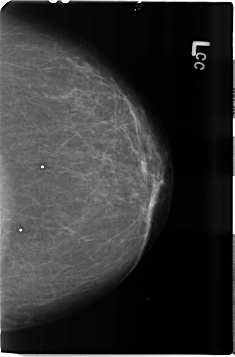

B_3506_1.LEFT_CC

LEFT_CC LINES 4632 PIXELS_PER_LINE 3048 BITS_PER_PIXEL 12 RESOLUTION 50 NON_OVERLAY

B_3506_1.LEFT_MLO

LEFT_MLO LINES 4688 PIXELS_PER_LINE 3056 BITS_PER_PIXEL 12 RESOLUTION 50 NON_OVERLAY